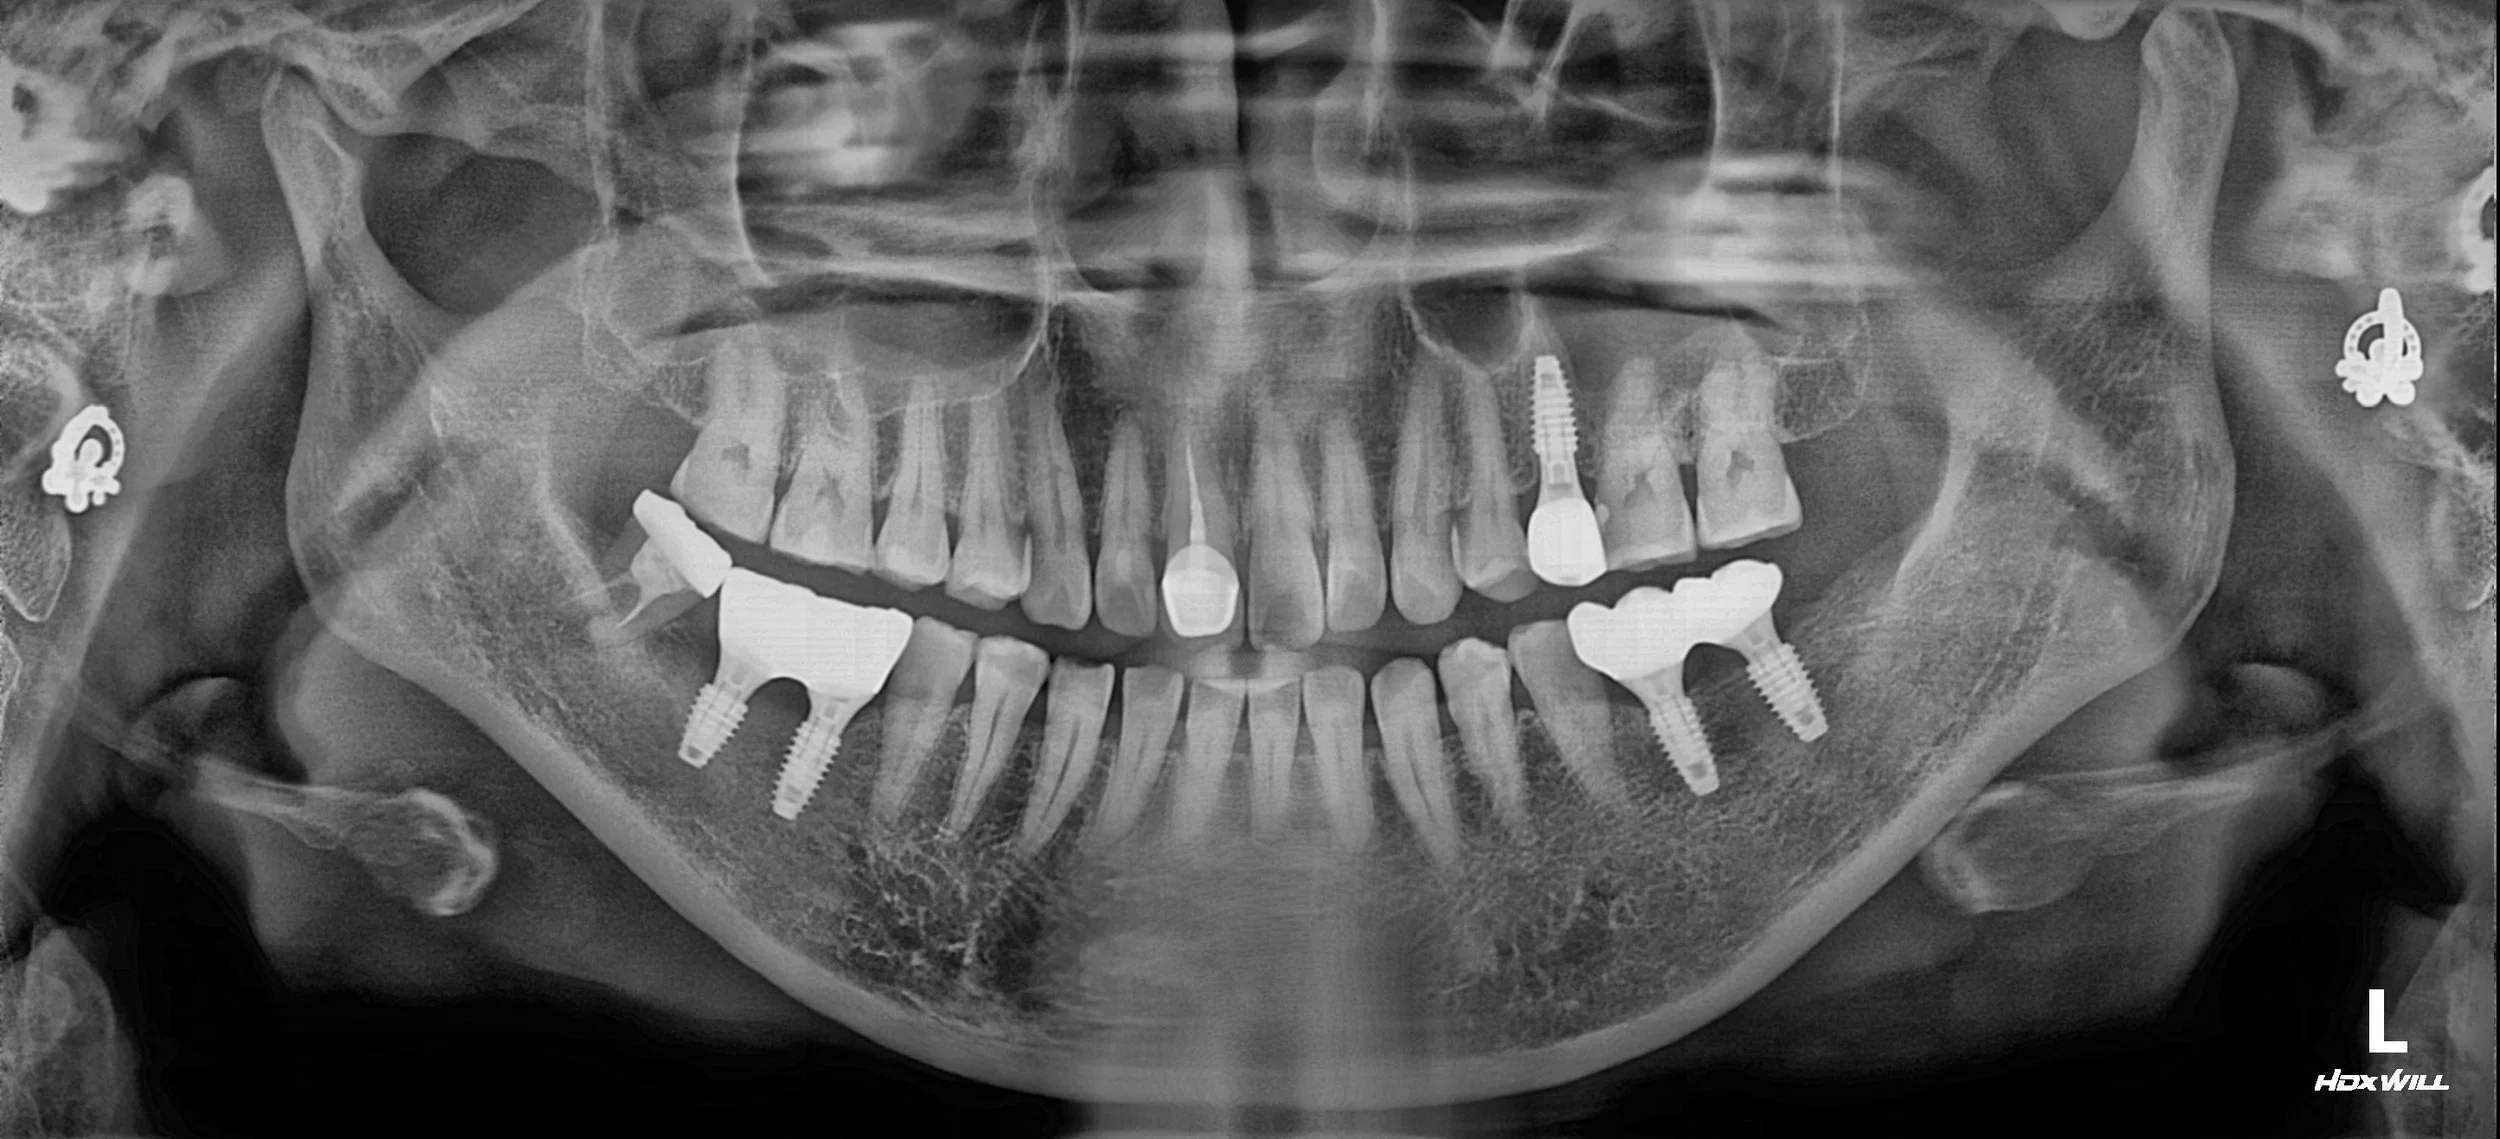

1. Interference Management & Implant Surgery: The primary interference (#48) was managed to allow the mandible to return to a more centered position. Dental implants were strategically placed in the edentulous posterior areas.

2. Slight VDO Elevation: Using provisional restorations, the vertical dimension was slightly elevated. This was critical to re-establish a harmonious occlusal curve and to compensate for the previous supra-eruption of the upper teeth.

4. Final Delivery: Once functional comfort was confirmed, the final restorations were delivered. The new occlusal scheme provides balanced bilateral support, protecting the joints and ensuring a stable, centered bite.

The patient achieved complete relief from her TMJ symptoms and regained full masticatory function with a stable, harmonized occlusion.